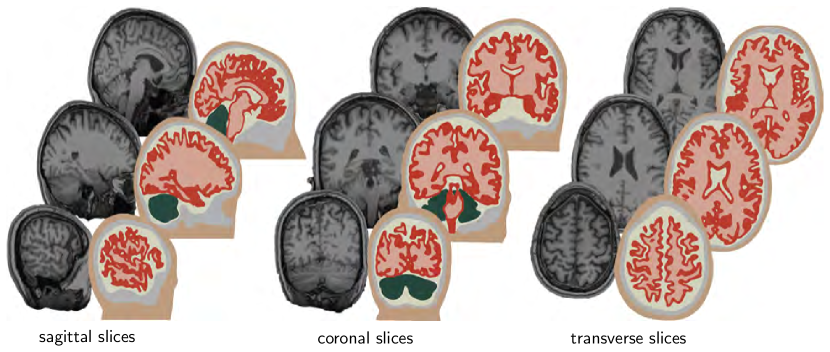

Figure 5 shows representative sagittal, coronal, and transverse slices of an adult female head that form the basis of our anatomic model. The brain has a total volume of 1,108cm3, a surface area of 1,673cm2, and an average cortical thickness of 0.252mm. Our magnetic resonance image set contains a total of 190 slices in the sagittal plane at a spacing of 0.9 mm. Each slice has a matrix representation of 256 ×\times 256 pixels with an in-plane resolution of 0.9 mm ×\times 0.9 mm saggar15 . From the magnetic resonance images, we create a personalized high-resolution anatomic model of the brain using the ScanIP software environment of Simpleware young08 . This semi-automatic software iteratively produces an anatomically detailed and geometrically accurate three-dimensional reconstruction of all relevant substructures including the cerebral gray and white matter, the cerebrospinal fluid, the cerebellum, the skin, and the skull cotton16 . From these substructures, we create a finite element model with 1,275,808 linear tetrahedral elements and 241,845 nodes using the finite element meshing tool of Simpleware weickenmeier16b . We import our head model into the finite element software package Abaqus, in which we prescribe the constitutive models as well as the boundary, contact, and loading conditions abaqus14 .

Refer to caption

Figure 5: Personalized decompressive craniectomy model. Magnetic resonance images (left) and computational model (right). Anatomically detailed and geometrically accurate three-dimensional reconstructions of the individual substructures including the gray matter (red), the white matter (pink), the cerebrospinal fluid (beige), the cerebellum (green), the skin (brown), and the skull (gray) shown for selected sagittal, coronal, and transverse slices.